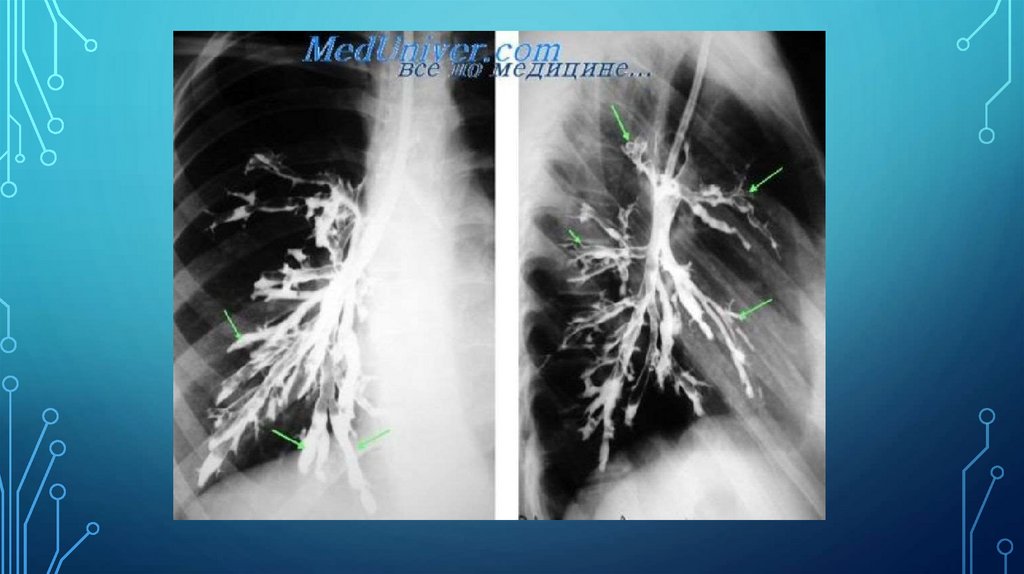

• Бронхография. Деформация просвета (втягивание или выпячивание) и расширение бронхов

цилиндрического типа с различной глубиной контраста («обрыв» бронхов любого порядка), искривление и

обнажение стволов бронхов, эмфизематозных участков, линейное затемнение — пневмофиброз. Бронхография

выявляет деформацию стенки бронхов в виде различной степени втягиваний и выпуклостей, неровных контуров бронхиальных

ветвей, их обнажения, обеднения мелких бронхиальных ветвей, фрагментов контрастного вещества (деформирующий

бронхит).